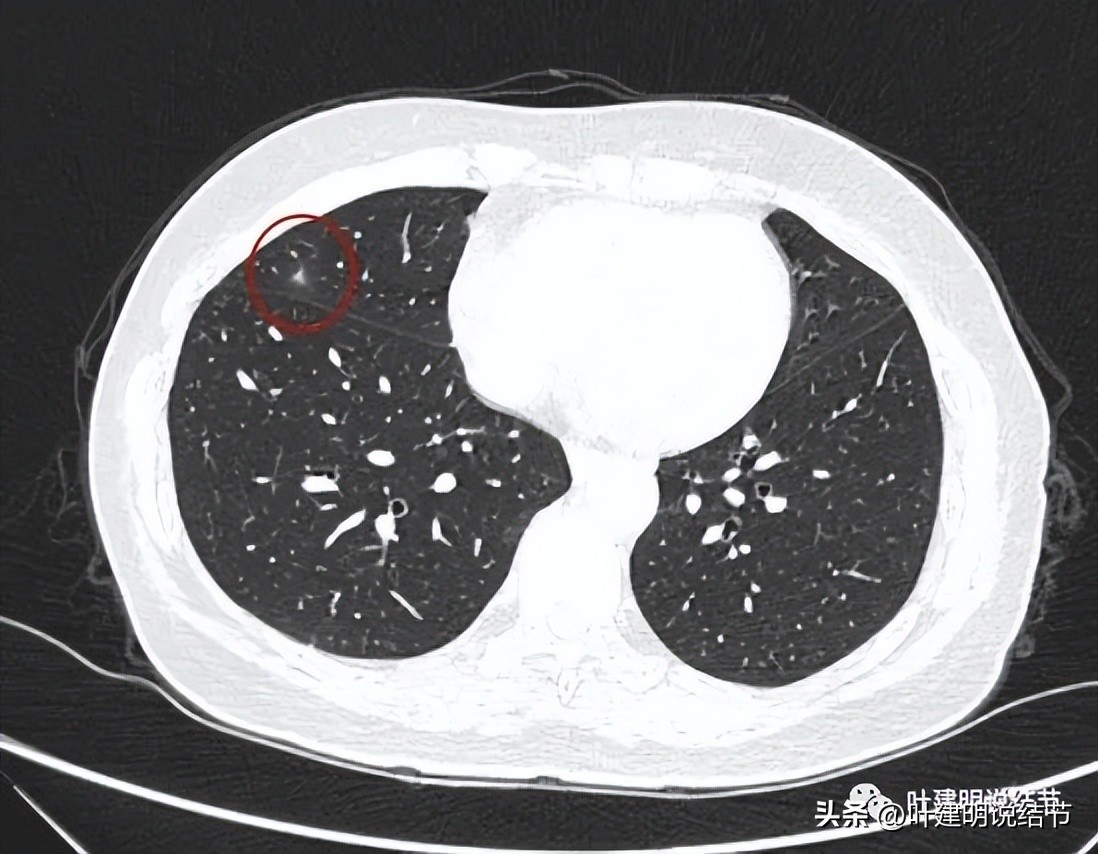

上图是右中叶的病灶,边缘偏模糊的磨玻璃影。因为最早于2018年时是报了右中叶有小结节,所以此处也要注意一下。

此灶中间有偏高密度,磨玻璃部分边缘不太清楚,显得瘤肺边界欠清。

灶内条状偏高密度可见。

叶间胸膜感觉略有点牵向病灶,但不厉害。

边缘区是磨玻璃成分,更靠胸膜处似乎还有卫星病灶。

右叶单按此次的影像来看,感觉倾向慢性炎些,毕竟收缩力弱、有卫星灶、轮廓虽清,但瘤肺边界欠清,磨玻璃部分密度较低,中间实性部分密度偏高但呈条状。